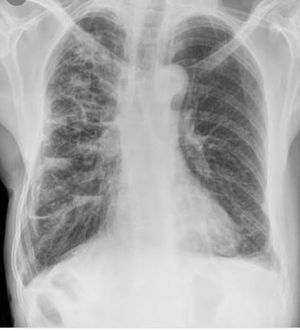

Diagnosis?

Heart failure with pulmonary edema

Miliary TB

Pulmonary edema

It's bronchiectasis